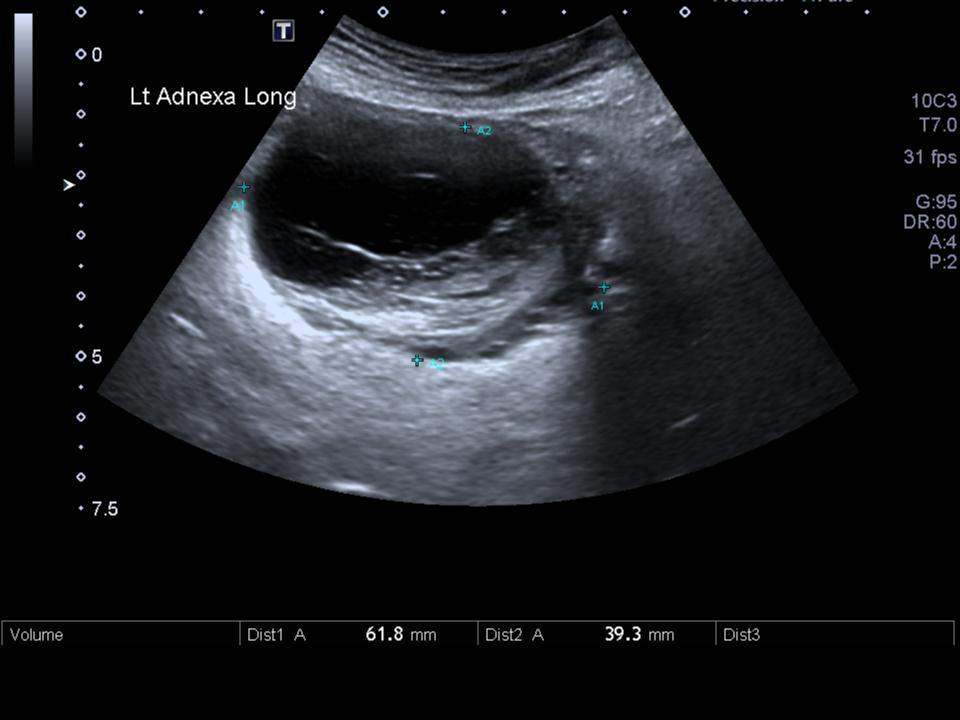

- Transvaginal sonography or CT-scan: to rule out tubo-ovarian abscess, particularly in more ill-appearing patients and those who do not respond to outpatient treatment

- Tubo-ovarian abscess.